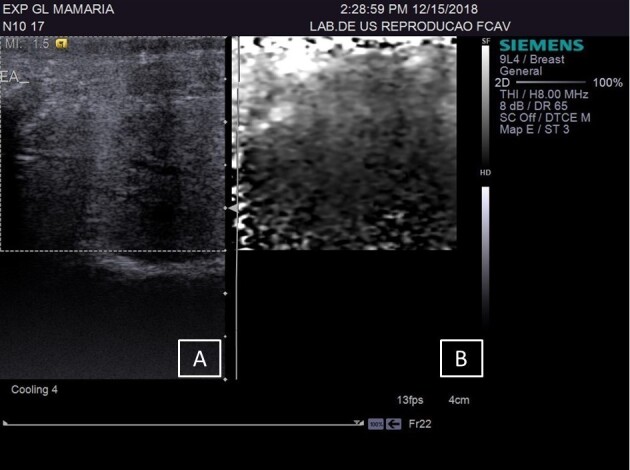

该研究旨在评估在乳腺实质和乳腺上淋巴结中使用Acustic Radiation Force Impulse(ARFI)弹性成像技术检测自然感染慢性纤维性病变绵羊活动性乳腺炎的情况。研究人员选取了 27 只雌性绵羊,采集了 48 个乳腺的 B 型超声波和 ARFI 弹性成像图像,获得了定性(回声和回声纹理)和定量(剪切率、深度和长短轴比)变量。这些乳腺被分为三个实验组:对照组(CG)--健康动物;LSCC--出现纤维性病变和 SCC(体细胞数)小于 500 x 103 cls/mL的动物;HSCC:出现纤维性病变和 SCC(体细胞数)大于 500 x 103 cls/mL的动物。在腺体的健康区域,LSCC 的剪切波速度(SWV)比 HSCC 高(P=0.04)。将 LSCC 组和 HSCC 组的纤维化部位与各自的正常部位进行比较时,两组的剪切波速度都有所增加:LSCC(p= 0.0007)和 HSCC(p= 0.0001)。将 LSCC 和 HSCC 的纤维化区域与 CG 实质进行比较,LSCC(p=0.001)和 HSCC(p=0.0001)的纤维化区域均有所增加。B 型超声显示,在活动性亚临床乳腺炎病例中,淋巴结以低回声为主,短/长轴比值降低。CG 组与 HSCC 组(P=0.02)和 GC 组与 LSCC 组(P=0.04)相比,乳腺上淋巴结的 SWV 增加。B 型超声波检查有助于评估乳腺实质,但不建议将其作为独立的诊断技术使用。ARFI 弹性成像显示了区分亚临床乳腺炎和痊愈乳腺炎的潜在临界点,突出了其作为区分正常区域和纤维实质区域工具的重要性。虽然由于样本量的限制,本研究没有确定具体的临界点,但更大样本量的进一步研究可以探索和确定这些关键临界点。

The aim of the study was to evaluate the use of Acustic Radiation Force Impulse (ARFI) elastography in mammary parenchyma and supramammary lymph nodes, for detection of active mastitis in sheep with naturally infected chronic fibrous lesions. 27 female sheep were included and B-mode ultrasound and ARFI elastography images were obtained, acquiring qualitative (echogenicity and echotexture) and quantitative (shear rate, depth and short/long axis ratio) variables of 48 mammary glands. The glands were divided into three experimental groups: control group (CG) - healthy animals; LSCC- animals that presented fibrous lesions and SCC (somatic cell count) less than 500 x 103 cls/mL; HSCC: animals that presented fibrous lesions and SCC (somatic cell count) more than 500 x 103 cls/mL; The qualitative variables using B-mode ultrasonography, including echotexture and echogenicity, showed no significant differences between the evaluated groups and tissues (p = 0.9336 and p = 0.233, respectively) .In healthy areas of the gland, it was an increasing in shear wave velocity (SWV) in LSCC than in HSCC (p=0.04). When comparing the fibrosis in the LSCC and HSCC groups with their respective normal areas, the velocity increased in both groups: LSCC (p= 0,0007) and HSCC (p= 0,0001). When comparing the areas of fibrosis in LSCC and HSCC with the CG parenchyma, there was an increase in LSCC (p=0.001) and HSCC (p=0.0001). B-mode ultrasound indicate predominance of hypoechoic echogenicity in lymph nodes and reduced short/long axis ratio in cases of active subclinical mastitis. The supramammary lymph node showed increased SWV when comparing the CG with HSCC groups (p=0.02) and GC with LSCC (p=0.04). B-mode ultrasonography is useful for evaluating the mammary parenchyma, however, its application as a standalone diagnostic technique is not recommended. ARFI elastography indicates potential cutoff points for differentiating subclinical mastitis from healed mastitis, highlighting its importance as a tool for distinguishing normal areas from fibrous parenchymal areas. While this study did not establish specific cutoff points due to sample size limitations, further research with larger sample sizes could explore and define these critical thresholds.